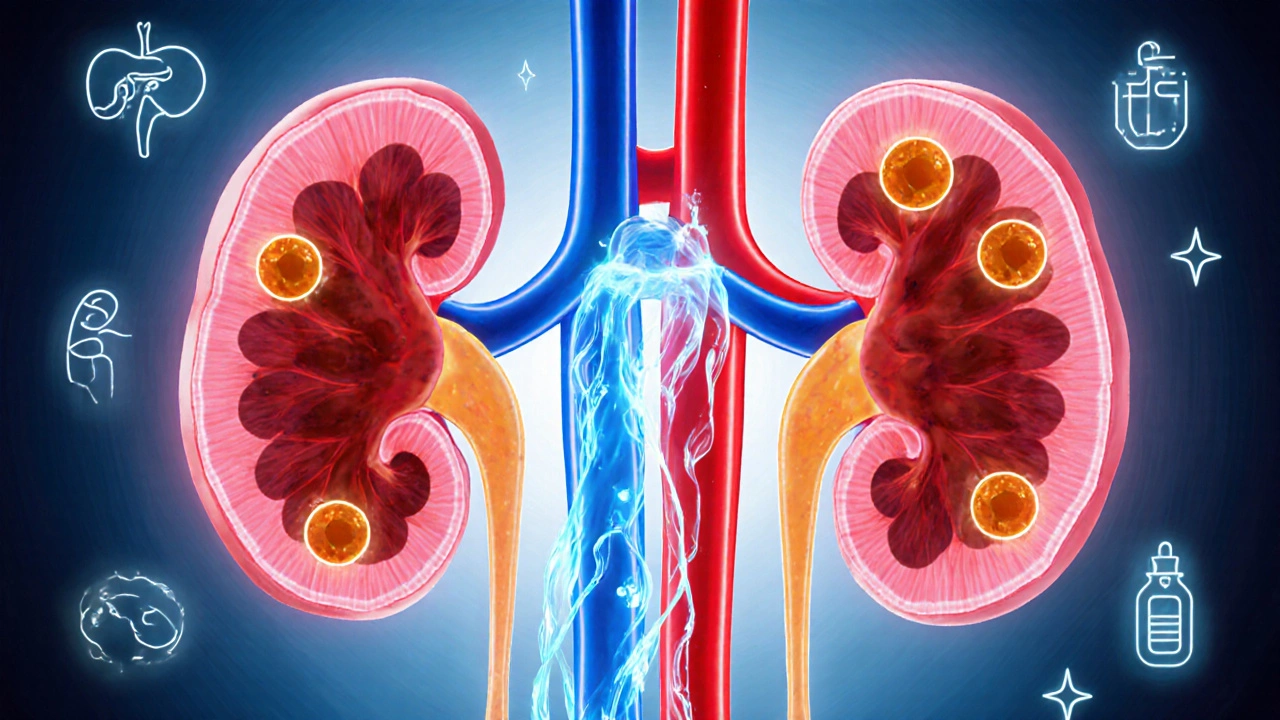

If the pancreas can’t make enough insulin, or the body becomes resistant to it, glucose builds up. This condition is called hyperglycemia a sustained blood sugar level above the normal range (generally > 180mg/dL after meals). Over time, repeated spikes damage blood vessels, nerves, and organs, leading to complications like heart disease, kidney failure, and vision loss.

When blood sugar spikes, the kidneys try to flush the excess glucose out through urine. That extra load means you’ll head to the bathroom more often - sometimes every two hours, even if you haven’t had much to drink.

Elevated glucose weakens white blood cells, making it harder for your body to fight off germs. Small cuts on the feet or hands can linger for weeks, and you might get frequent boils or fungal infections.